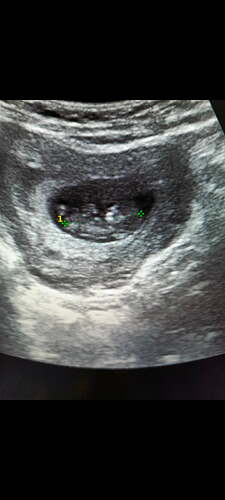

Bunada cinsiyet tahminin de bulunur musunuz

Kız bebiş kesesi gibi ![]()

Erkek bebiş kesesi gibi

Erkek bebiş kesesi gibi ![]()